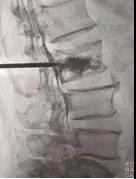

手術(shù)中情況

4月21日,我院骨科孫守全專家小組為老人進(jìn)行了PKP手術(shù),術(shù)后當(dāng)天老人腰背部疼痛銳減,己能坐起吃飯。術(shù)后第二天就能下床大小便,生活已能基本自理。七天后,老人順利出院!按照常規(guī)治療方法,需臥床三個月,還有可能出現(xiàn)尿路感染、肺部感染等等一系列并發(fā)癥。這結(jié)果與現(xiàn)在相比真有天壤之別!據(jù)了解,PKP手術(shù)為脊椎的微創(chuàng)手術(shù),手術(shù)時間短、創(chuàng)傷小,出血少,止痛效果明確,恢復(fù)比較快。尤其是對于高齡衰弱的患者而言,采用PKP手術(shù)治療,患者承擔(dān)的手術(shù)風(fēng)險極大地減少,并且避免了長期臥床所導(dǎo)致的潛在并發(fā)癥。但該手術(shù)部位鄰近脊柱總神經(jīng),需要施術(shù)者嫻熟的手術(shù)技巧和細(xì)心大膽的手術(shù)操作。我院骨科在濰坊市較早引入椎體成形術(shù),目前已經(jīng)為近千名老人解除了"腰痛"病痛。